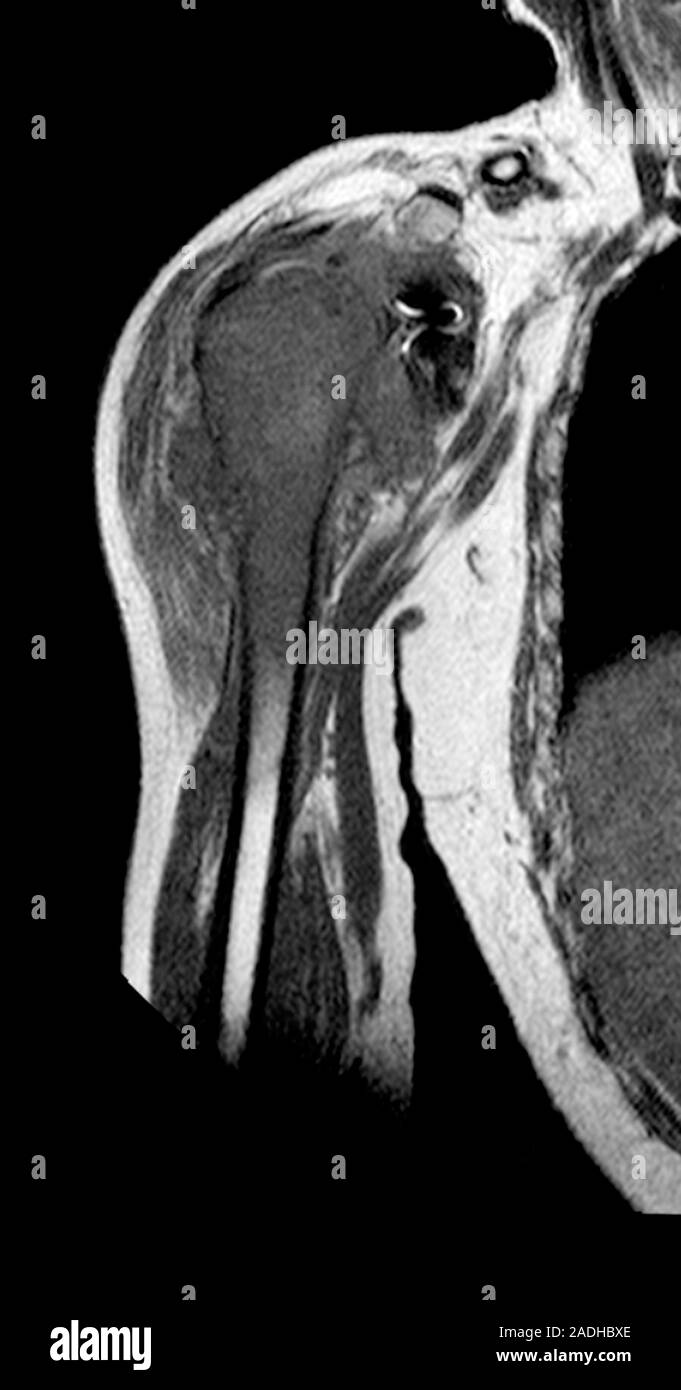

of the right scapula in the preoperative coronal MRI Chondrosarcoma Bone Scan Symptoms include bone pain, a lump or. Chondrosarcoma is the most common primary bone cancer in adulthood, and. Extraskeletal cases are extremely rare. Chondrosarcoma is a rare type of bone cancer that develops in cartilage cells. A ct scan of the chest should be performed in all patients to detect the presence of pulmonary metastases. Chordoma arises from the persistent. Chondrosarcoma Bone Scan.

From www.alamy.com

Bone cancer. MRI resonance imaging) scan of the right Chondrosarcoma Bone Scan Chondrosarcomas are a group of rare bone cancer tumors that begin in your cartilage. It is the most common bone cancer found in adults. Chondrosarcoma is a rare type of bone cancer that develops in cartilage cells. Extraskeletal cases are extremely rare. Here, sarcoma medical oncologist anthony. Symptoms include bone pain, a lump or. Chondrosarcoma is a rare cancer that. Chondrosarcoma Bone Scan.